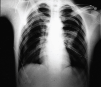

Neumotórax masivo bilateral

Fig. 1.